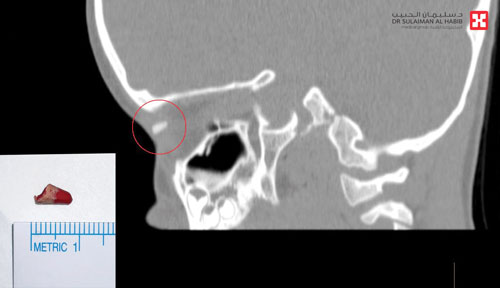

وقال الدكتور محمد صالح استشاري طب وجراحة العيون، رئيس الفريق الطبي المعالج أنه عند وصول الطفل للمستشفى وإجراء الفحص السريري تبين أن لديه جرحاً صغيراً بالجفن العلوي بالعين اليمنى مما سبب انتفاخاً متزايداً في منطقة العين، وقد قرر الفريق الطبي إخضاع الطفل لفحوصات دقيقة بالأشعة السينية والتصوير الطبقي (C.T Scan) والتحاليل المخبرية. وأضاف أن نتائج الفحوصات كشفت عن وجود جسم غريب بطول 1 سم وعرض 4 مللم في محجر العين اليمنى بالمنطقة الواقعة ما بين العظم والعين، مع عدم وجود أية عدوى أو التهابات وسلامة المقلة. وفي ضوء النتائج قرر الفريق الطبي التدخل الجراحي عاجلا للحيلولة دون إصابة الطفل بالعدوى، أو حدوث أية مضاعفات قد تصل إلى فقدان الرؤية لا سمح الله.

وقد أجريت عملية جراحية للطفل تحت التخدير الكامل استغرقت «35» دقيقة، وتم خلالها استئصال الجسم الغريب وتنظيف مكان الجرح، ونقل بعدها الطفل إلى جناح التنويم. وتبين من المعاينة للجسم الغريب أنه قطعة خشبية من بقايا قلم تلوين كان الطفل يلهو به. وأضاف د. محمد صالح أن جهود الفريق الطبي تكللت بالنجاح ولله الحمد وبدون مضاعفات، وأن الكشوفات الأولية التي أجريت للطفل بعد العملية أظهرت تحسن حالته، وقد خرج من المستشفى في اليوم التالي للعملية وهو بصحة جيدة.